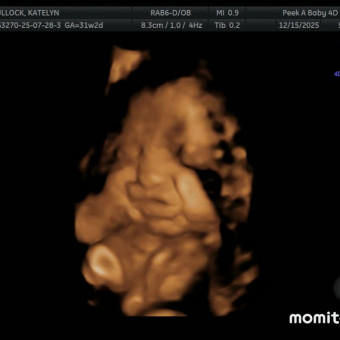

Kanaan Joy’s Baby Registry

Katelyn & Justin Bullock

Thank you so much for celebrating our sweet girl with us! Baby Kanaan Joy is already so loved, and we are incredibly grateful for your prayers, kindness, and support. Feel free to browse to get an idea of the items we like, want, and love as we prepare for her arrival.💗